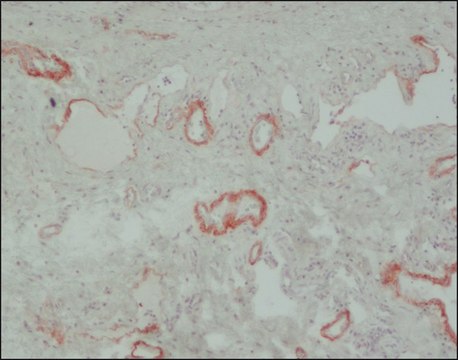

immunohistochemistry: 5-10 μg/mL using pronase-retrieved formalin-fixed, paraffin-embedded human tonsil sections

• in Immunohistochemistry

Tenascin-C (TN-C) functions in cell adhesion, fibroblast migration, and other processes related to tissue remodeling and wound healing. It has been proposed that actively growing, migrating and differentiating epithelial sheets can produce factors such as (Transforming growth factor beta) TGF-β to stimulate tenascin expression. Neo-expression or increased expression of tenascin has been found in the stroma of various tumors and during normal tissue repair. Intracytoplasmic tenascin immunoreactivity has been detected in malignant melanomas and in lung carcinomas, and it serves as a marker of stromal element proliferation in invasive breast carcinomas. High-molecular mass tenascin isoform plays a role in generating a permissive environment for proliferation, invasion, and metastasis of neoplastic epithelial cells. Human tenascin contains an Arg-Gly-Asp (RGD) sequence which may function in cell adhesion and mediates cell attachment through an RGD-dependent integrin receptor.